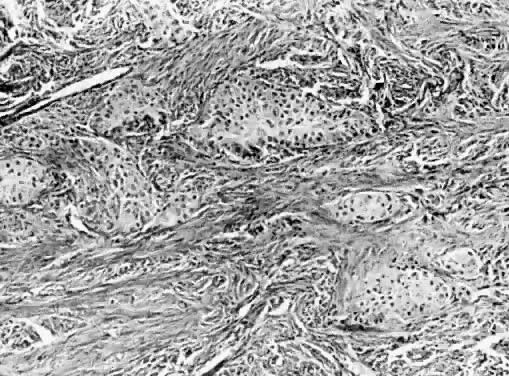

Endometriosis is discussed elsewhere in these volumes, but endometriomas also tend to be intraovarian. Benign endometrioid-type adenofibromas may occur in the ovary or elsewhere in the pelvic soft tissues, principally in the broad ligament. Clinically, they may be confused with myomas until examined histologically. Brenner tumors occur in borderline and malignant forms, but the vast majority are benign (Fig. 6). They consist of squamous-type epithelial nests in a fibrous or thecomatous stroma, and although there are exceptions, they tend to be on the ovarian surface. Accounting for only a small percent of all ovarian tumors, they are bilateral about 5% of the time. Most are small and are discovered incidentally. The stroma is often hormone producing, and Brenner tumors, for this reason, have been associated with clinical signs and symptoms of hyperestrogenism, including hyperplasia and endometrial cancer. Alternatively, the stroma may be fibrotic and calcified.

Fig. 6. Brenner tumor. Islands of uniform epithelial cells in dense fibrous stroma (hematoxylin and eosin stain, x125).

The appearance of squamous metaplasia in mucinous tumors has led some to believe that Brenner tumors routinely arise in this manner. Indeed mucinous and Brenner tumors are often mixed. Additional speculation about the origin of Brenner tumors has been occasioned by the fact that the epithelium in the nest is often transitional in type rather than squamous. Many such neoplasms are, for this reason, termed urothelial. In any case, the epithelial nests are clearly continuous with the ovarian surface.32 This is another example of an altered site giving rise to an altered form of differentiation.